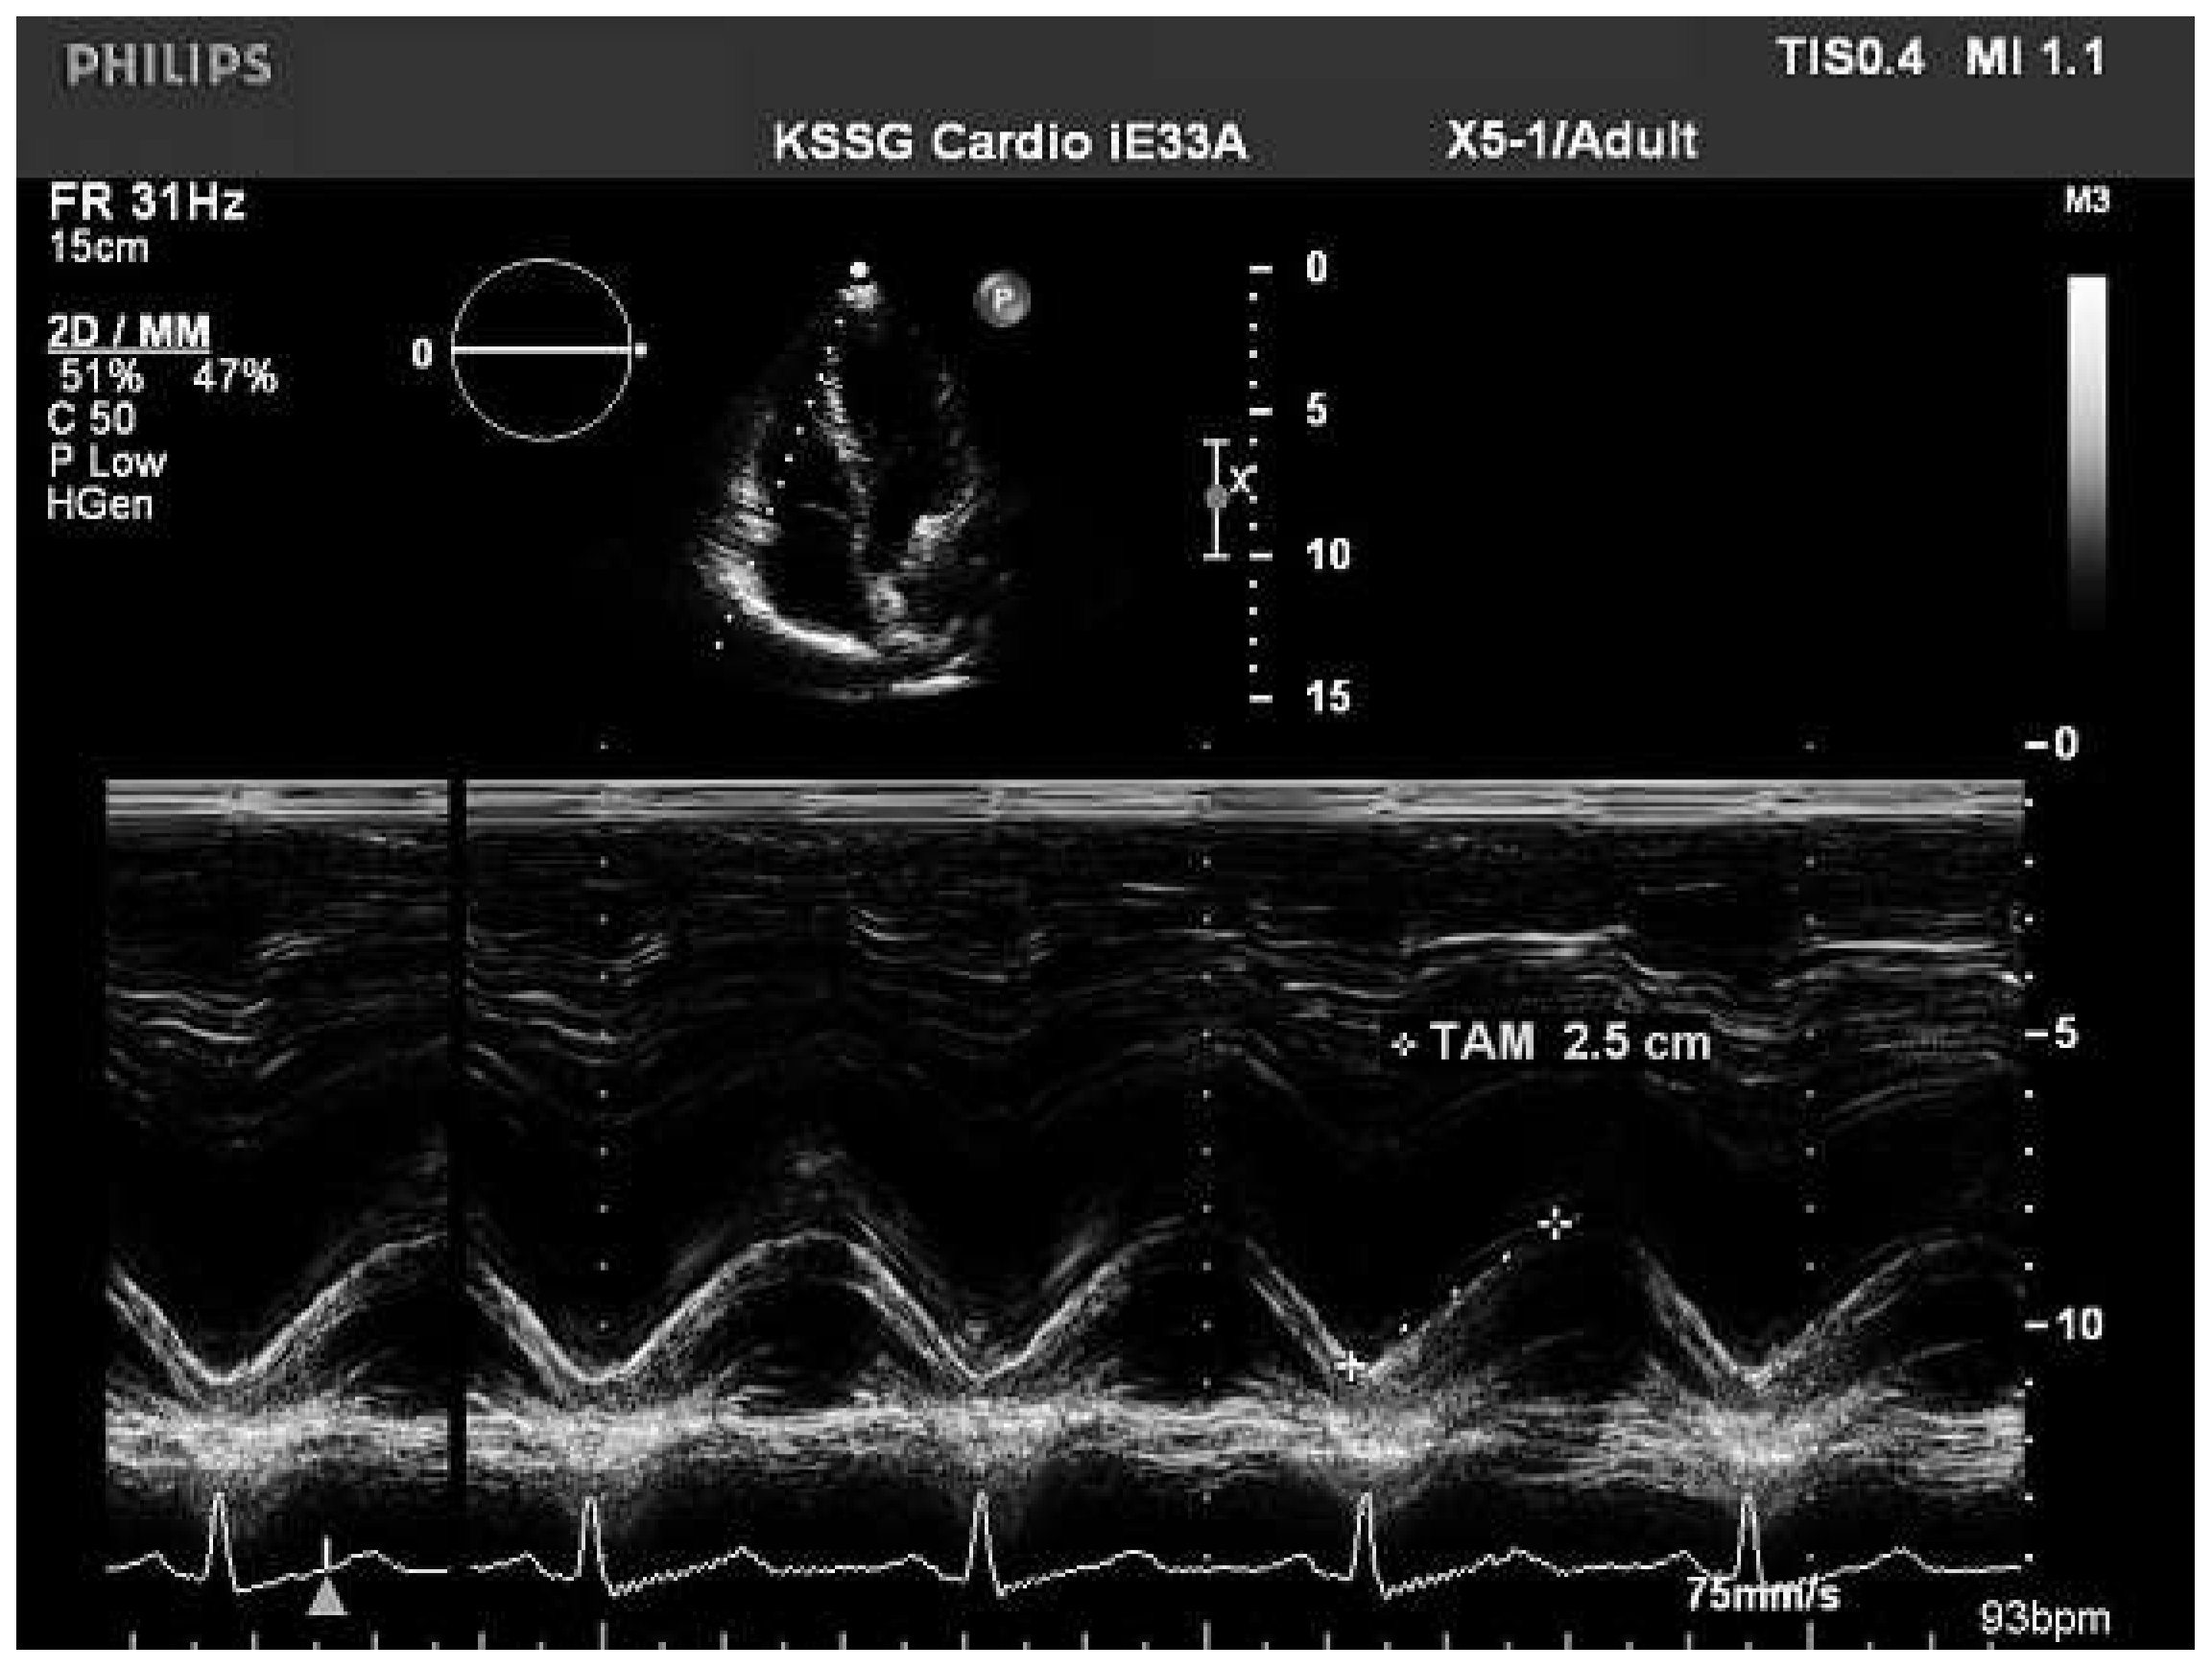

Assessment of the right ventricular function in M-mode (tricuspid annular excursion, RV outflow fractional shortening)

- Pavlicek, M.; Wahl, A.; Rutz, T.; de Marchi, S.F.; Hille, R.; Wustmann, K.; Steck, H.; Eigenmann, C.; Schwerzmann, M.; et al. Right ventricular systolic function assessment: rank of echocardiographic methods vs. cardiac magnetic resonance imaging. Eur J Echocardiogr. 2011, 12, 871–880. [Google Scholar] [CrossRef] [PubMed][Green Version]